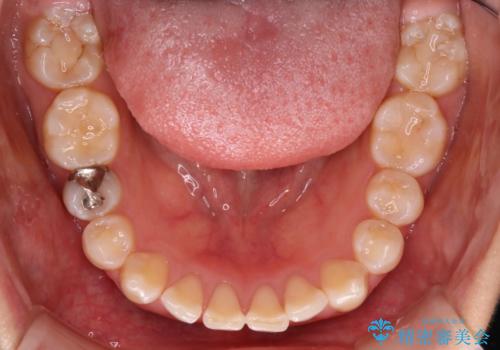

【ワイヤー矯正】前歯が出てるのをなおしたい。

- 前歯の凸凹を主訴に来院されました。

見た目だけではなくかみ合わせも良くなったと満足して頂きました。